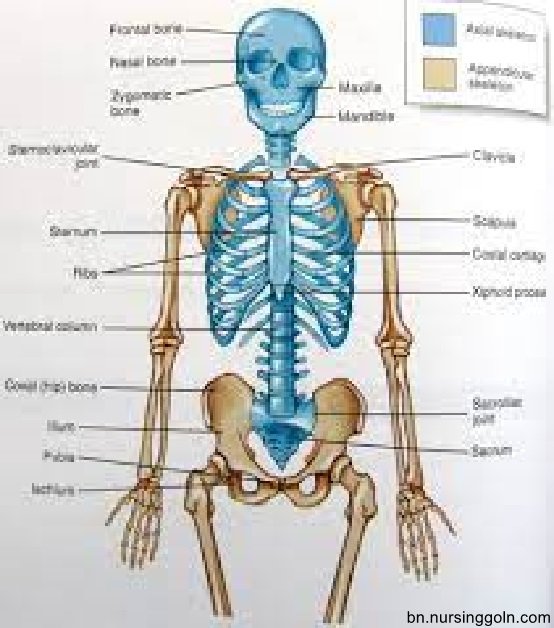

সেবাদানের জন্য মানব শরীর সম্পর্কে সুস্পষ্ট ধারণা থাকা জরুরি। দেহের গঠন, কার্যপ্রণালী, গুরুত্ব, অঙ্গপ্রত্যঙ্গ ও অন্নসমূহের জ্ঞান, সেবা গ্রহণকারীর চাহিদা অনুযায়ী কাজের পরিধি ও পরিকল্পণা করার পূর্ব শর্ত।